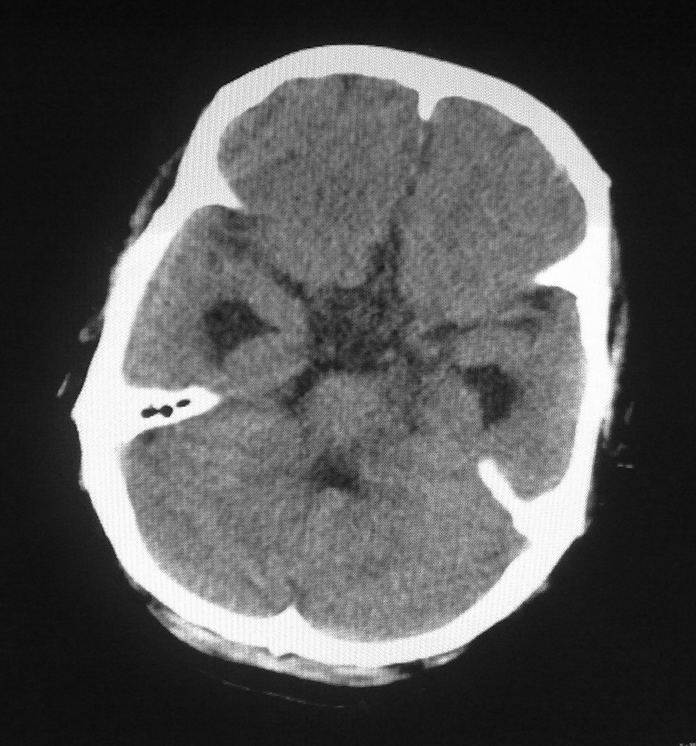

男,61岁,发热,有脑出血病史。

右侧基底节,放射冠软化灶,胼胝体发育不良 脑积水原因待查。

右侧基底节及放射冠软化灶,脑积水,四脑室显示不清,导水管梗阻?建议mri!

梗阻性脑积水,出血后粘连所致

1)右侧基底节区、右侧放射冠及右侧丘脑软化灶。2)脑积水。